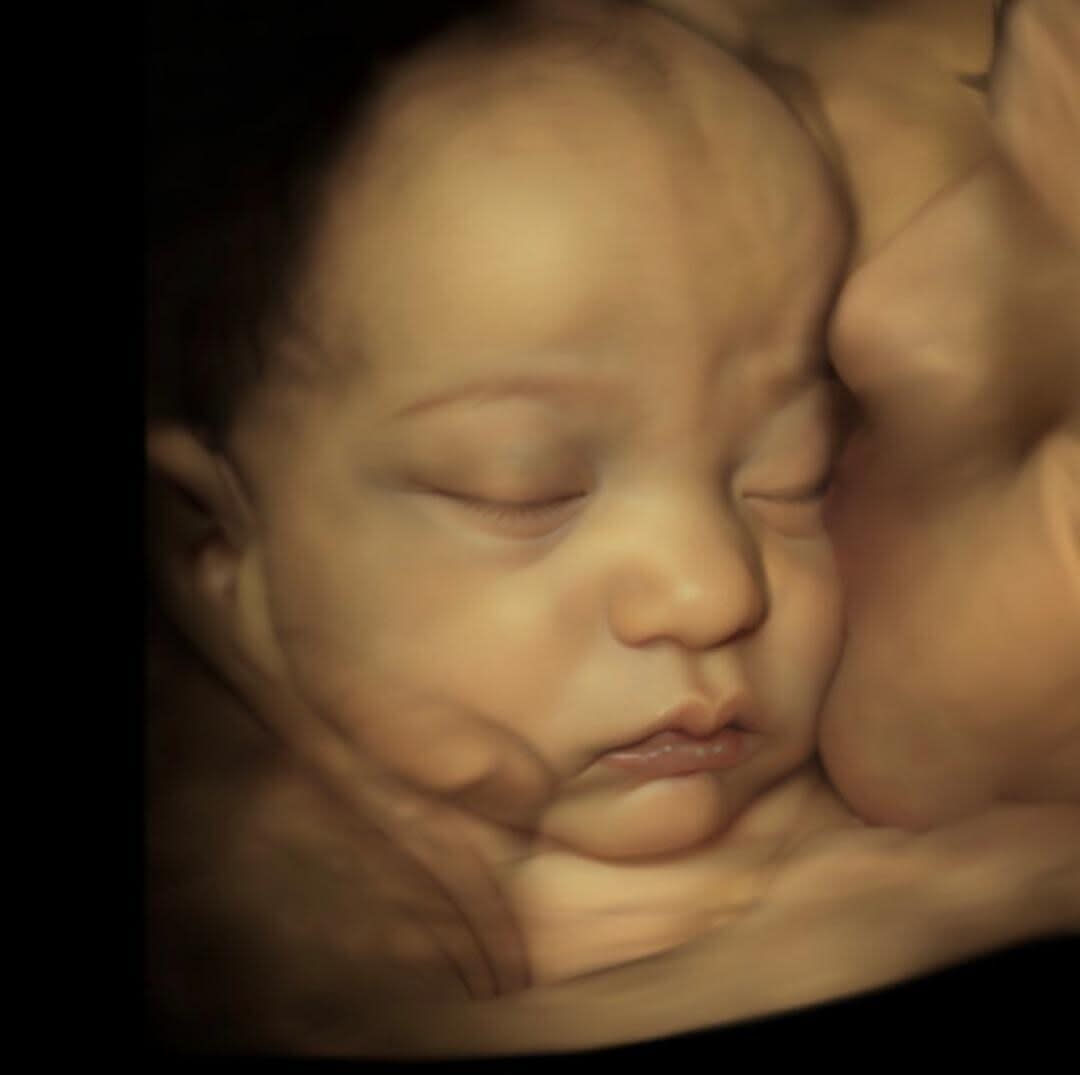

8K Enhanced Images

Grimsby Numi Scan are proud to use 8K technology combined with advanced AI techniques to digitally enhance your ultrasound images. This optional extra enhances 4D images to truly reflect your babies features and create a life like image for parents to be.

This service is carried out after your 4D ultrasound and is not new ultrasound technology but a way of upgrading and enhancing your 4D images. The turn around time is just 24 hours so we won't keep you waiting too long!

This service will work best on 26 weeks gestation and onwards.